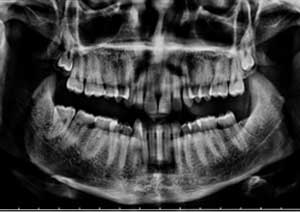

Radiographie

Radiographie avant